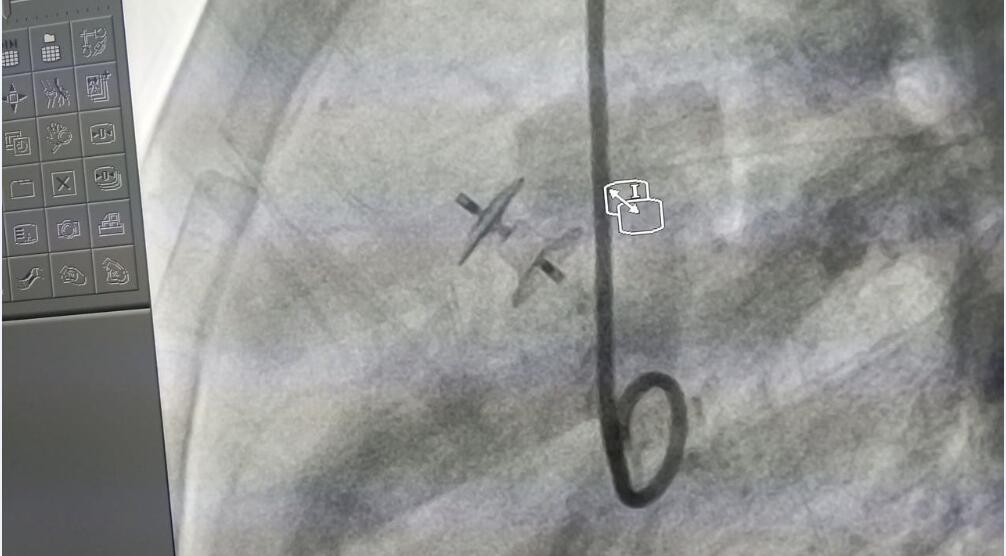

该病例为多孔膜周部室距离缺损并伴有室缺瘤。术中丈量患者左室面缺损直径为3.6 mm,右室面缺损直径为3.4mm,缺损长度为5.3mm;级丛拥牟∏槭沟醚∪〈尘猜鲺杈锻ü倚氖也嗫捅涞眉饶烟。在Dr.Worakan的领导下,重要术者Dr.Supapon选择了俄罗斯贵宾会集团科技公司型号为LT-MFO-5-3的KONAR-MF?多职能封堵器,通过动脉蹊径开释成功。术后造影显示,患儿缺损部位封堵齐全,无残存分流。

(Dr.Supapon使用KONAR-MF?多职能封堵器进行手术封堵)